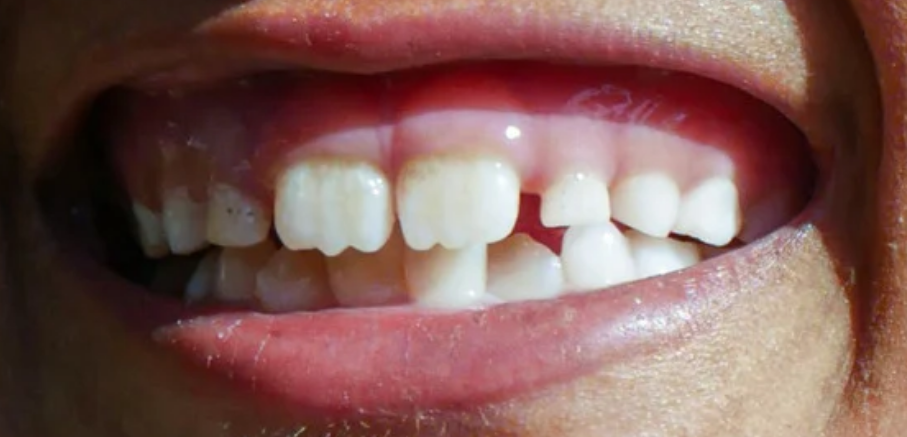

During primary school years, most children transition from a full set of deciduous teeth to a full set of permanent teeth. By around the age of 13, most children will have their full set of 28 permanent teeth, except for the third molars, or wisdom teeth, which may erupt later. At the stage when a child has both deciduous and permanent teeth, it is called the 'mixed dentition stage'.

Between the ages of approximately six and 12 years, children have a mixture of permanent and deciduous teeth (mixed dentition). By the age of 13, most children have all their permanent teeth except for the third molars (wisdom teeth).

- Carers may ask about mamelons, which are the three small bumps or ridges often seen on the biting edges of newly erupted permanent incisors. Mamelons usually wear down over time with normal chewing. They are rarely seen on deciduous teeth, as these ridges typically wear away during the teething process.